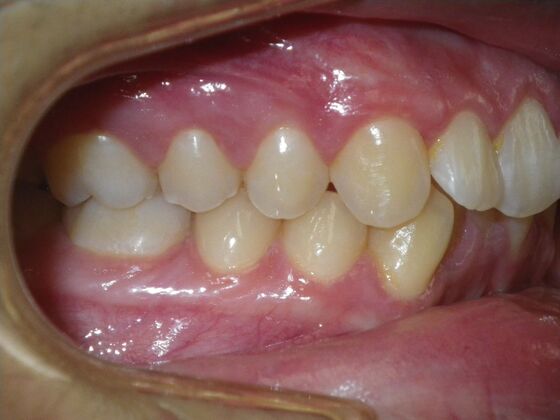

Patient presents with constricted upper and lower arches that will need expansion as well as slenderizing (IPR) to correct upper and lower anterior crowding.